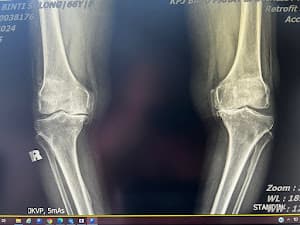

Desember 2022 Saya punya pengalaman sendiri melahirkan putri saya dengan Dr. Norliza.. MasyaAllah beliau sangat baik, sopan, dan sabar.. insya Allah lain kali kami akan terbang kembali dari Arab Saudi ke Batu Pahat hanya untuk pelayanannya.. insya Allah.. terima kasih Dokter atas pengertian dan pelayanan Anda yang luar biasa. Juli 2023 adik bungsu saya juga menjalani operasi, tidak ingat nama dokternya. Tapi hasilnya juga sangat baik. Dokter bahkan menjelaskan mengapa dan bagaimana beliau membantu dalam kasusnya, dan beliau juga menindaklanjuti sendiri menanyakan kondisi adik saya setelah operasi.. Alhamdulillah beliau sudah pulih. Maret 2024.. ibu saya menjalani operasi besar penggantian lutut total. Oleh Dr. Ezat.. Masya Allah Dr. Ezat ini sungguh luar biasa. Beliau melayani ibu saya seperti anaknya sendiri dan stafnya juga, jika mengadu ada masalah pada ibu saya, mereka seperti saudara kandung. Masya Allah. Hasil operasinya sangat luar biasa.. alhamdulillah.. masalah lutut ibu saya sudah stadium 4-5. Memang sudah tidak bisa digunakan. Jadi alhamdulillah beliau sedang pulih dan yang terbaik adalah operasinya alhamdulillah ternyata tidak sesakit yang kami dengar dan bayangkan. Setelah satu bulan lebih ibu saya bisa berjalan tanpa alat bantu. Sangat senang dan bersyukur dengan hasilnya. Alhamdulillah. Saya sangat menyarankan siapa pun yang punya masalah tulang, lutut untuk menemui Dr. Ezat ini. Anda tidak akan kecewa dengan pelayanannya.. Insya Allah nanti saya akan membagikan pengalaman ibu saya di FB. Terima kasih atas pelayanan Anda yang luar biasa Dr. Ezat. Selamat KPJ BP, Anda punya spesialis yang sangat baik!